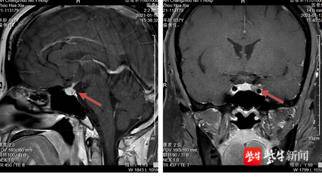

今年年初,王女士在一次体检中发现自己的血压偏高,收缩压竟达156mmHg,还没“忧伤”多久,她的脸上又长出了痤疮和小胡子。她辗转去过多家医院,做过不少治疗,也吃了很多药,但效果都不是很明显。在朋友建议下,她来到常州一院。结合相关影像资料,内分泌代谢科蒋晓红主任医师建议住院治疗。经内分泌代谢科和神经外科多学科联合会诊,最终诊断为皮质醇增多症(库欣病),神经外科邵耐远主任医师建议神经内镜微创手术治疗。

邵耐远介绍,皮质醇增多症是垂体性、肾上腺性、异位性等三种独立病理综合征的总称,其临床症状主要由皮质醇分泌过多所致。王女士此次发病的病因是ACTH腺瘤,占垂体性皮质醇增多症的80%左右。此病不仅会导致向心性肥胖和精神障碍,还会引发女性出现月经失调、多毛和痤疮等症状,男性出现阳痿、精液稀少、性欲减退等症状。同时,由于蛋白质过度分解,患者还会出现肌萎缩无力、骨质疏松、腰背痛、皮肤变薄、面红、腹部紫纹等症状。血压持久升高,还可能影响心、肾功能和眼底血管。

“ACTH腺瘤首选手术切除,假包膜外全切肿瘤可达到保留垂体功能和内分泌治愈的双重目的。手术需彻底切除肿瘤,对医生的手术技能和精准度要求很高。”邵耐远组织科室讨论,制定完善的手术方案和应急预案。随后,他和团队站上手术台,经过2小时的努力,手术顺利切除肿瘤。术后复查,ACTH值顺利降至正常范围。